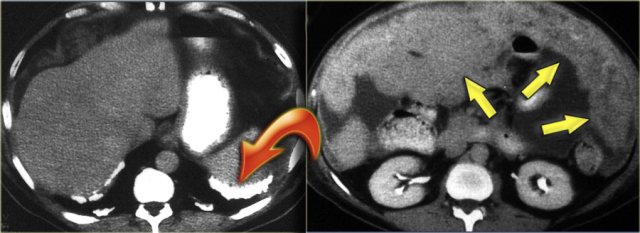

Pseudomyxoma peritonei (2)

On the left another case of pseudomyxoma peritonei.

There is hardly any scalloping of the liver.

Notice the thickened falciform ligament.

There is a mucocele of the appendix (arrow).

This finding is only rarely seen.

There is compression of the mesentery resulting in a thickened cake-like hyperdense mesentery (arrow).

There are also some calcifications.

Pseudomyxoma peritonei is often confused with mucinous carcinomatosis.

Unlike carcinomatosis it does not have true omental tumor deposits presenting as omental cake or peritoneal tumor deposits.